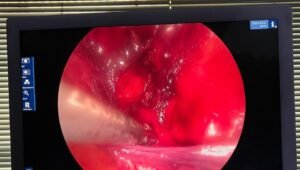

کراچی: سندھ گورنمنٹ قطر اسپتال میں جدید لیپرواسکوپک سرجریز کا سلسلہ دوبارہ شروع ہوگیا ہے۔ اسپتال میں پہلی بار 58